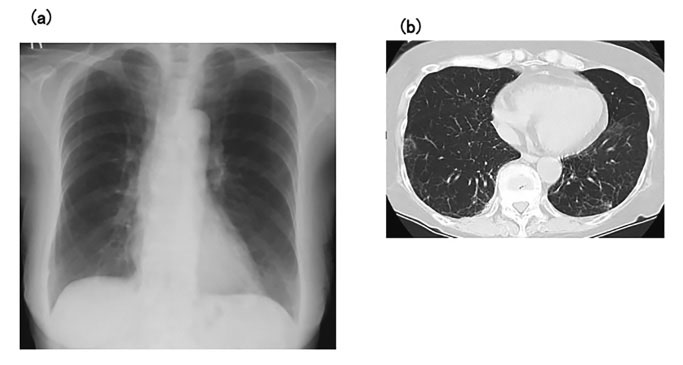

Prednisolone 40 mg/day was administered postoperatively for 7 days, and the patient’s respiratory condition improved after extubation. Her condition remained good after gradual tapering of the prednisolone, with almost normal appearances of both lung fields on chest X-ray and CT, despite no specific treatments for LPD (Fig. 3). The prednisolone dose was tapered to 15 mg/day on day 40, and the patient was discharged from hospital on day 46 (Fig. 4). The patient’s condition remained good after discharge. Whole-body CT revealed no findings associated with recurrence of LPD, and she was thus considered to have achieved CR, although no re-examination of bone marrow aspirate was performed.

(a) Chest X-ray at discharge shows almost normal results for both lungs. (b) Chest computed tomography at discharge shows disappearance of abnormal shadows from the lung fields.